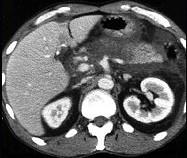

问题 女,45岁,急性上腹部持续性疼痛,程度剧烈,放射到胸背部,恶心、呕吐,白细胞计数增高,血尿淀粉酶升高,影像所见如图,最可能的诊断是 ( )

选项 A.急性单纯性胰腺炎 B.急性出血坏死性胰腺炎 C.慢性胰腺炎 D.胰腺癌 E.胰腺脓肿

答案 B